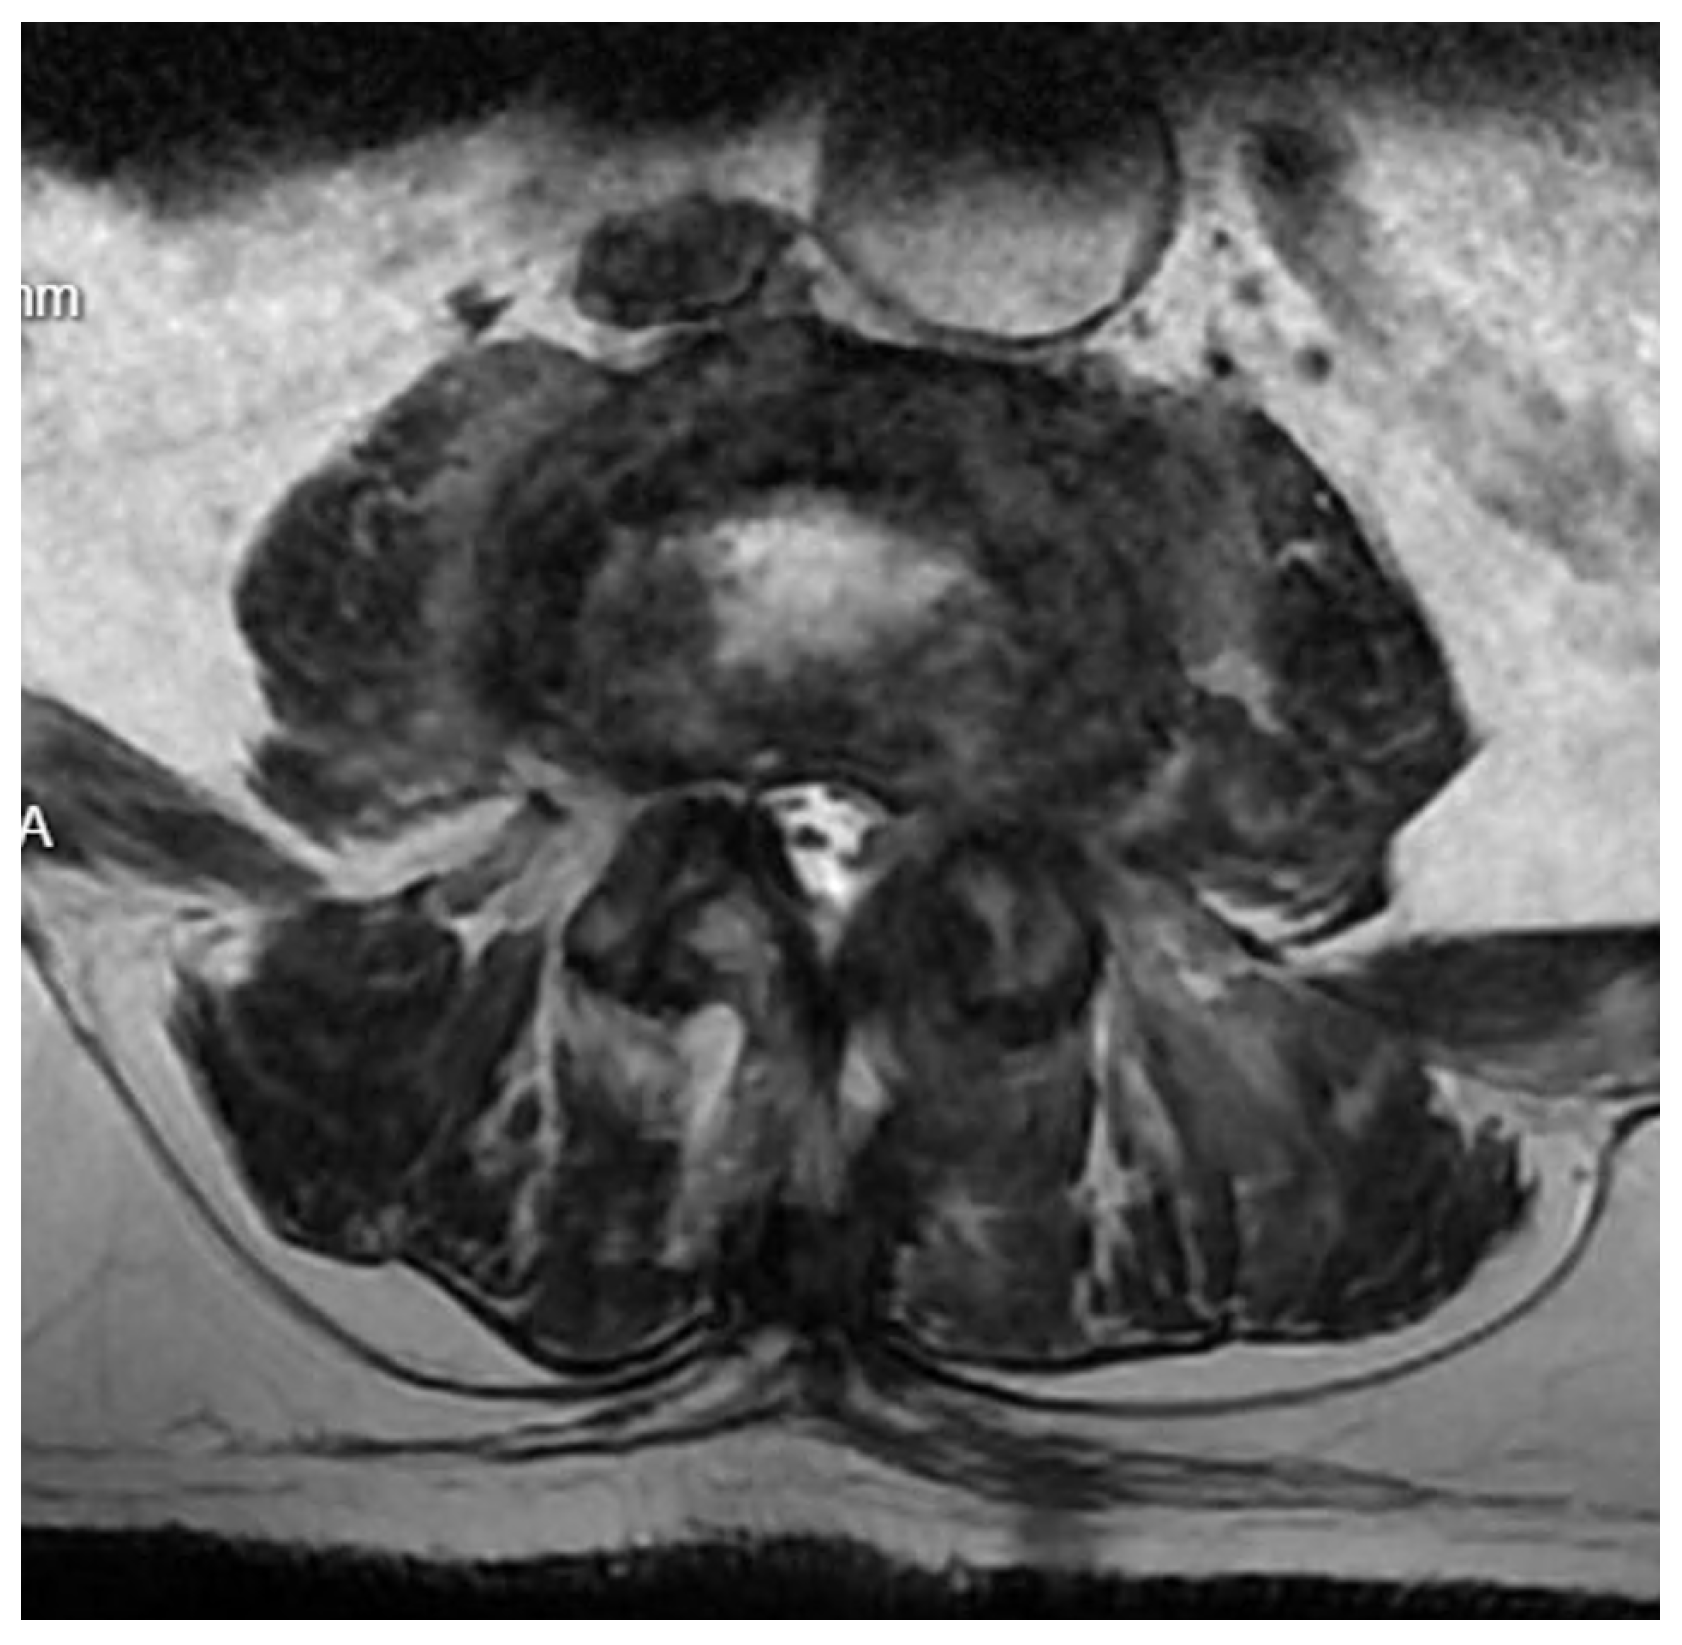

Diagnostic Evolution: After a week of conservative treatment without improvement, a follow-up MRI was ordered(Figure 3), which unambiguously identified spondylodiscitis with an abscess in the canal, causing compression of the dural sac and both S1 nerves (Figure 4). The patient’s pain syndrome worsened significantly, VAS 9 in the lower spine, leading to her qualification for surgical treatment.

Figure 4. Pre-operative T2 axial MRI image at the L5/S1 level one week after admission to the neurology department.